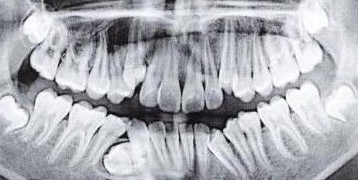

口腔CT犹如医生可透视的眼睛,通过CT

精确测量牙齿错位、歪斜的程度与角度;

同时3D扫描牙槽骨、颌骨等"脸型"骨架,

获得精准的数据。

口腔CT测量的牙齿、牙槽骨数据通过计算机

导入到"正畸软件"进行分析,精确算出矫正

所需的"生物拉力","靶向"到每一颗牙齿上。